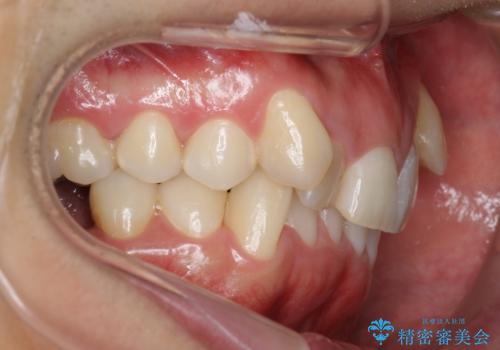

八重歯の矯正+歯のないところにインプラント

- 八重歯を主訴に来院。

下の歯がないところに、奥歯が倒れこんでいたため、矯正治療で倒れこんだ歯を起こして、インプラントを植立しました。

上の前歯が下の前歯に大きく重なっており、過蓋咬合を呈していました。

上顎の小臼歯2本、下顎の親知らずを抜歯しています。

八重歯の移動のため、矯正用ミニスクリューを使用しています。